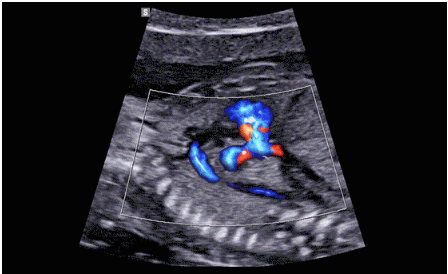

近日三星醫(yī)療推出了一款全新的母嬰超聲系統(tǒng)——Hera i 10。該款產(chǎn)品除了成像能力本身,人性化的座椅設(shè)計,探頭擺放位置等也是亮點之一。

Hera i 10繼承并升級了全球首款5D超聲“三星麥迪遜WS80A”的“晶體結(jié)構(gòu)”成像理念,即將CrystalBeam?波束形成技術(shù)、CrystalLive?超聲成像引擎、S-Vue Transducer?視覺傳感器集于一身,提供更清晰的圖像。

CrystalLive?是三星最新的超聲成像引擎,同時增強了2D圖像處理能力、3D渲染能力和彩色信號處理能力,能夠在復(fù)雜情況下提供出色的圖像性能,具備檢測外周血管、微循環(huán)血流的能力。